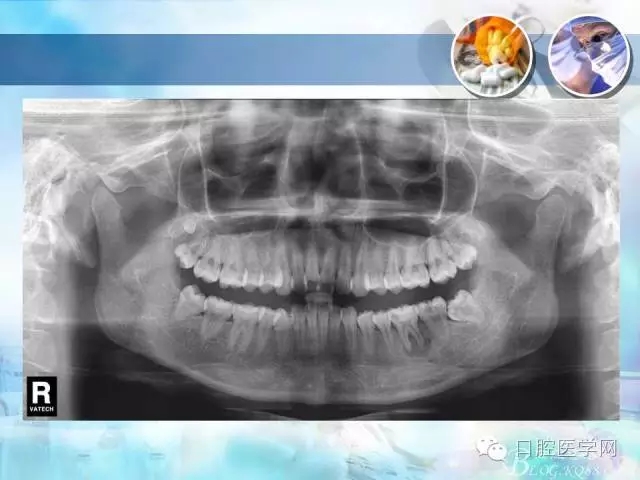

錯(cuò)合畸形中長(zhǎng)度不調(diào)的治療